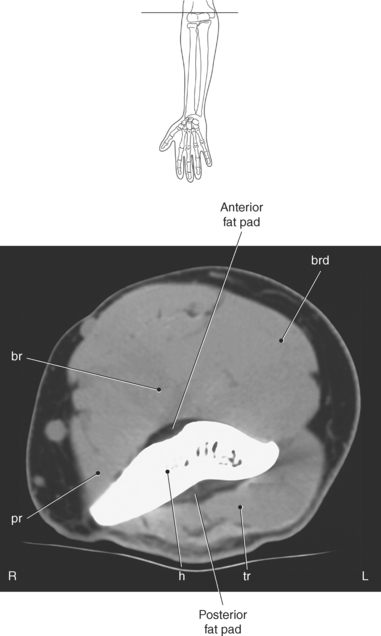

The entire elbow joint is surrounded by a relatively loose joint capsule that allows for the movements of flexion and extension. The joint capsule is weaker anteriorly and posteriorly but is reinforced medially and laterally by the strong radial and ulnar collateral ligaments (discussed in the next section). Located within the olecranon and coronoid fossas are fat pads that fill the space between the synovial membrane and joint capsule (Figures 9.77 and 9.78). The fat pads help cushion the area where the olecranon and coronoid processes move during flexion and extension of the elbow. There are two clinically important bursae located in the elbow: the olecranon bursa and the distal bicipitoradial bursa. The olecranon bursa is located within the subcutaneous tissue overlying the olecranon process (Figure 9.77). The distal bicipitoradial bursa lies between the insertion of the biceps tendon and the humerus.

Key: fl, Flexors; c, capitate; ex, extensor tendons; r, radius; l, lunate; D, dorsal interosseus muscles; P, palmar interosseus muscles.